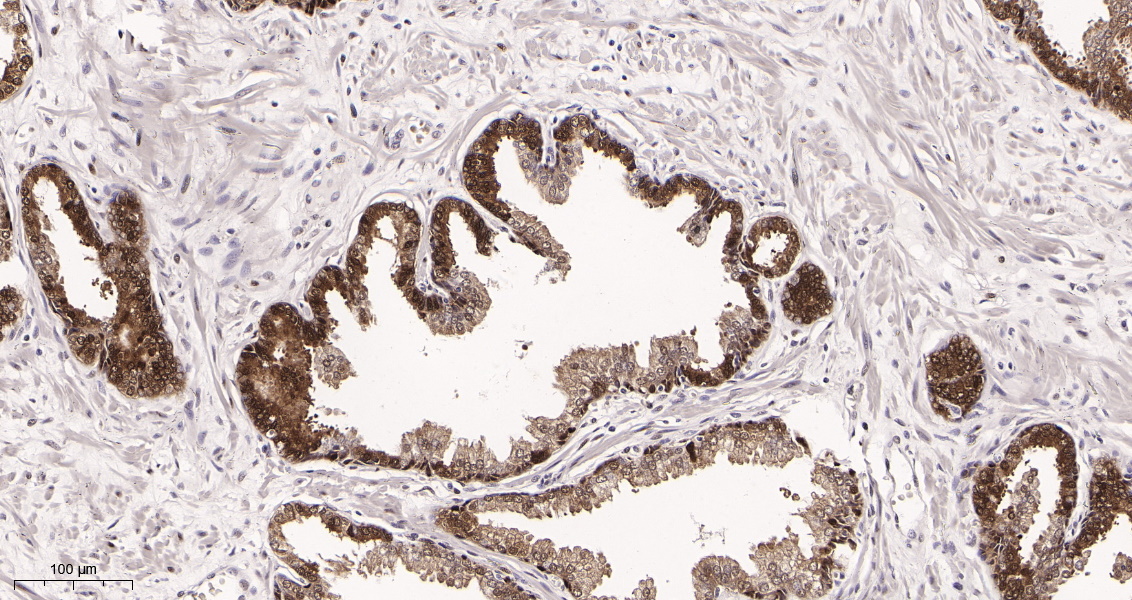

产品名称Hsp70 (4D5) Rabbit Monoclonal Antibody

推荐应用WB,IHC-P,IF-P,IF-F,IF-ICC,ELISA

稀释度IHC-P 1:400-1000, WB 1:1000-5000, IF-P/IF-F/IF-ICC 1:200-1000, ELISA 1:5000-20000